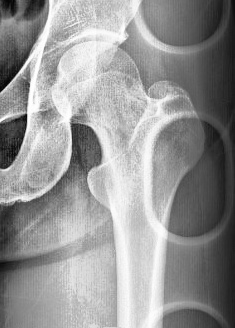

l_result_7สมชาย.jpg                      16-Apr-2024 04:27               31267